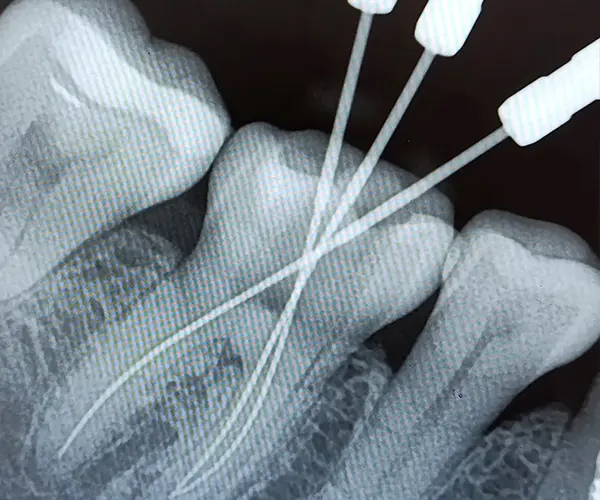

Контроль: рентгеновские снимки